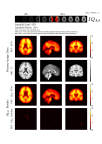

Introducing AmyloidIQ, a new and advanced algorithm that quantifies Amyloid scans for use in subject stratification and clinical trials of Alzheimer’s disease therapies. (Photo: Business Wire)

This novel algorithm calculates a single measure of the brain’s amyloid level denoted amyloid load, offering increased efficiencies within clinical imaging trials. The new method encodes expert domain knowledge into an artificial intelligence algorithm that can accurately calculate the level of amyloid plaques in the brain. Test data from the Alzheimer’s Disease Neuroimaging Initiative database containing over 900 [18F] Florbetapir scans were analyzed with the new method and resulted in a 50% increase in power over other existing methods. This technique opens the possibility of detecting smaller changes sooner, allowing clinical trials to run more efficiently and cost effectively by using reduced-size trials while achieving the same results.